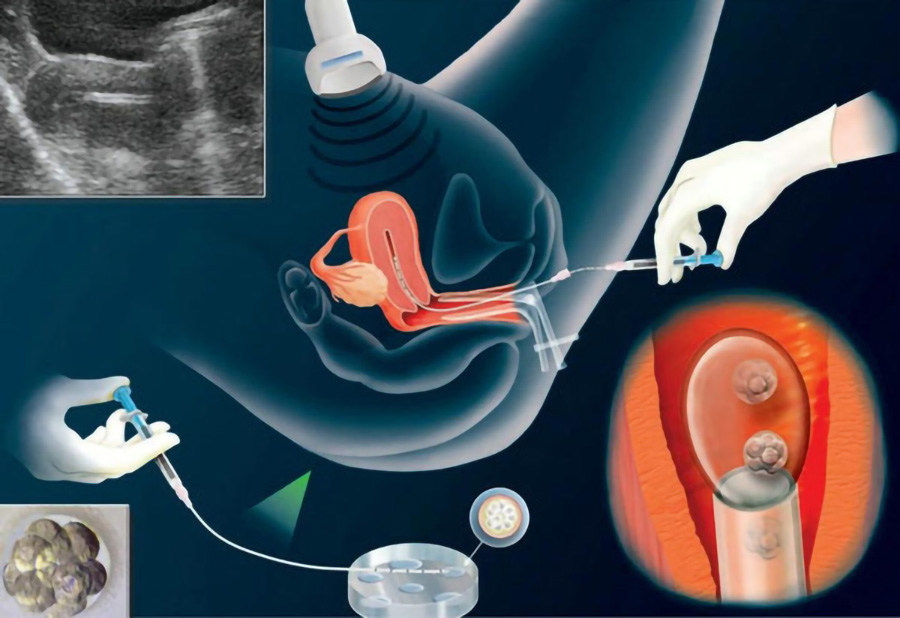

美国第三代试管婴儿即PGD/PGS基因检测技术,是指在胚胎移植前,提取胚胎的遗传物质进行分析,诊断是否存在异常,筛选健康胚胎进行移植,防止遗传病传递的方法。

赴美做试管,HRC专家会提取囊胚的4到8个外围细胞,用聚合酶链反应(PCR)、萤光原位杂交(FISH)等检测囊胚是否存在遗传病、染色体病等。

三、美国第三代试管婴儿的周期流程

2、促排取卵

HRC专家会根据女性的生育年龄、卵巢功能、激素水平、卵泡储备量、身高体重等情况,为其量身定制合适的促排卵方案,并使用经美国FDA监管认证的天然、无副作用的药物进行促排。在女性用药过程中,专家会实时跟踪监测,以了解卵泡的发育情况,确定女性对促排卵药物的反应程度,并及时调整用药剂量和时长,有效规避腹水、多囊卵巢等并发症的发生,确保女性身体健康。之后专家会在卵泡发育成熟时进行取卵,以获得多个优质卵子。

3、精卵结合

男性一般通过手淫法完成取精。完成取精后,专家会运用全新的Perecoll梯度离心精子洗涤技术对提取的精液进行洗涤和优化,去除死精、炎症细胞、精子抗体、碎片率高及活力低的精子,再通过高倍显微镜从中挑选出形态正常、活性强的优质精子。之后,HRC专家会借助显微操作系统将经洗涤优选过的精子直接注射到卵子内,使其跨越精子运动等一系列步骤,实现高达99%的卵子受精率。

4、囊胚培育

将受精卵放入培养皿培养后,第2~3天,受精卵会经过卵裂,分裂成由几个至十几个细胞组成的实心细胞团,形成早期的胚胎。第4天胚胎将发育形成桑葚胚,随后进入高速分裂期,细胞加倍分裂、增长,第5天就会分裂成由一百多个细胞组成的囊胚。

5、基因检测

养囊成功后,HRC专家会运用先进的第三代试管婴儿技术对囊胚进行基因检测,筛查囊胚染色体是否存在缺失、倒置、易位等异常情况,诊断其是否携带遗传缺陷基因或导致某种疾病的基因突变,从而筛选出健康的囊胚用以移植。

6、囊胚移植

囊胚移植前,专家会先对女性进行身体调理,在其子宫内膜厚度达到8~12mm、血流丰富且质地松软时,再将健康的囊胚移植到子宫腔内合适的位置,使之顺利着床,从而提高妊娠率。